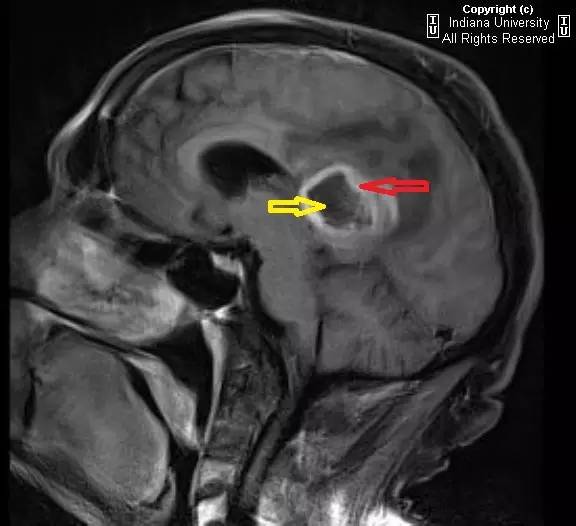

图 3 增强 MR 矢状位,病灶成周边强化(红色箭头),中央低信号表明有坏死性改变(黄色箭头)

可见一中心位于胼胝体压部的占位性病变,密度不均,中心为低密度,周围环状水肿。推压双侧脑室。右侧侧脑室室管膜极有可能受累。占位蔓延进入双侧半卵圆中心,右侧明显。MR 上,病灶成周边强化,中央无强化低信号表明有坏死性改变。

影像学上表现为厚壁、不规则、周边强化的肿瘤组织包绕中央坏死区。可见占位效应和瘤周水肿\肿瘤浸润。出血少见。肿瘤范围远大于 MR 上异常信号范围。